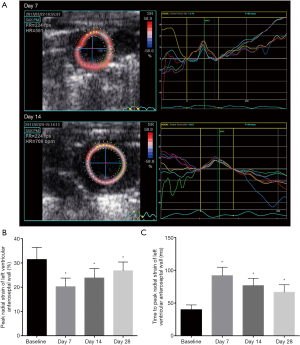

M-mode echocardiography detected LV deformation after MI

We discovered significant change in the LV deformation before and at day 7 and 28 post-MI (all n=24) (Figure 1A). M-mode tracings showed the values of EF (77.83%±3.24% vs. 37.33%±3.50%, P<0.01) and FS (40.33%±2.43% vs. 18.50%±0.96%, P<0.01) statistically decreased at the 7th day compared with the baseline group. After that, EF (44.17%±2.67% vs. 37.33%±3.50%, P<0.01) increased on the 28th day, compared with the 14th day tracings (Figure 1B). In addition, compared with day 14, FS (22.33%±2.43% vs. 18.50%±0.96%, P<0.01) significantly increased on day 28 (Figure 1C). M-mode imaging showed cardiac function dropped after MI and improved after 1-month repatriation.

We investigated the role of two-dimensional STE in early and comprehensive assessment of regional LV function after MI, and assessed the efficacy and safety of S100A4-shRNA in cardiac fibrosis after MI in mice. Firstly, M-mode imaging verified LV systolic function significantly declined after MI, and then improved 1 month later (Figure 1). Secondly, STE was more effective in the early assessment of cardiac deformation on the 14th day post-MI compared with conventional echocardiography (Table 2, Figure 2). Furthermore, LV global and regional systolic function statistically improved in the MI+S100A4-shRNA group by M-mode echo and strain analysis (Table 3, Figure 3). In addition, western blotting, Masson’s trichrome staining, and immunohistochemistry showed the efficacy of S100A4-shRNA in attenuating cardiac fibrosis after MI (Figure 4).